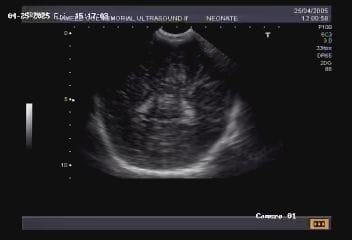

Neuro-sonography of the neonatal brain in cases of neonatal fits,

birth asphyxia,

meningitis,

hydrocephalus and shunts.